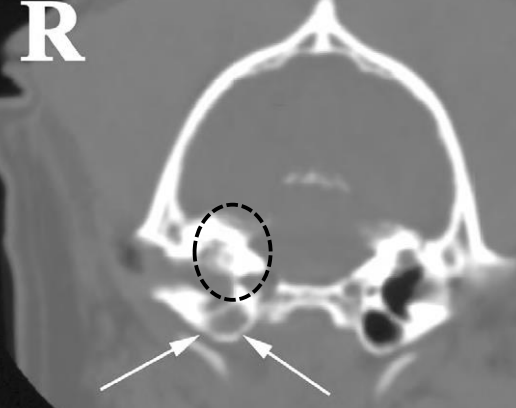

- ๋ฐฉ์ฌ์ , CT : concurrent otitis media, calcification, bone lysis (neoplasia)

์ด๋๊ฐ ๋ผ์ฒ๋ผ ๋ณด์.

์ผ์ชฝ tympanic cavity ๋ ์ ์ / ์ค๋ฅธ์ชฝ์ ๊ฝ ๋งํ ์๊ณ , ๋ผ๋ ์์.

์ค๋ฅธ์ชฝ์ ์ค์ด๋ก ๋์ด๊ฐ๊ธฐ ์ ์ ๋นจ๋ฆฌ ์กฐ์น ํ์ / ์ผ์ชฝ์ ์ค์ด๊น์ง ์ด๋ฏธ ์งํ / ๋๊ทธ๋ผ๋ฏธ๋ petrous temporal bone; lysis๊ฐ ์ผ์ด๋ ๊ฐํต์ฑ ์๋ ๊ฒ์ฒ๋ผ ๋ณด์ - ์ข ์ ์์ฌ